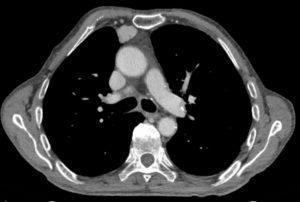

All three patients were found to have thymoma, which is a tumour in the thymic gland. They found that PIT-1 is expressed in these thymoma cells. CTLs then targeted PIT-1 and this caused the autoimmune response. When the researchers removed the thymus from patients with the autoimmune disease, the levels of anti-PIT-1 antibody and the effects of the CTLs specific to PIT-1 were greatly reduced. However, at 2 years post-thymus removal, there was no detectable improvement in pituitary function.